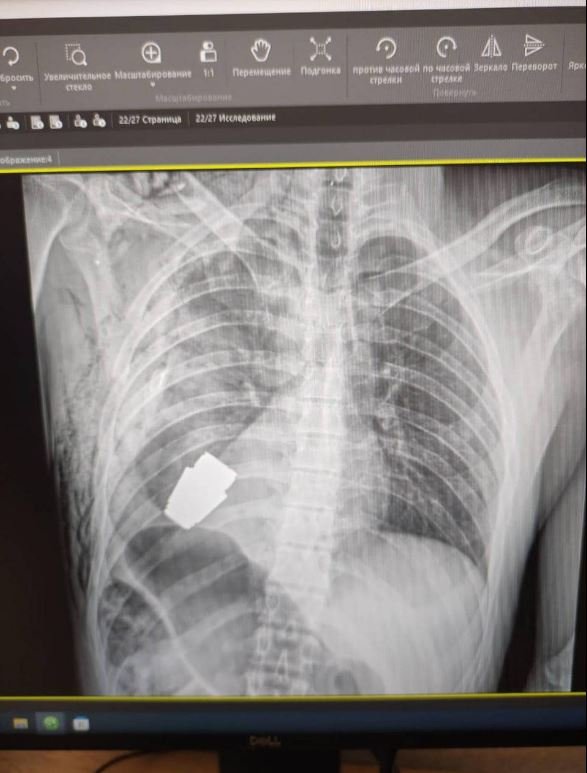

«Подивилися знімки, з’ясували, що в тілі снаряд. Рішення оперативно ухвалював безпосередньо Андрій Верба. Викликали саперів, вони відповідали за безпеку медперсоналу», – розповіла нам у коментарі про деталі Євгенія Слівко.Оперувати самостійно вирішив Андрій Верба – генерал-майор та досвідчений хірург ЗСУ. Операція відбувалася без електрокоагуляції.«Усе зшивалося вручну, оскільки граната могла детонувати в будь-яку хвилину», – пояснює Слівко.

Граната залишалася біля серця. За словами радниця, поранений був важким, але стабільним. Операція відбулася успішно, і військового вже відправили на реабілітацію та відновлення.